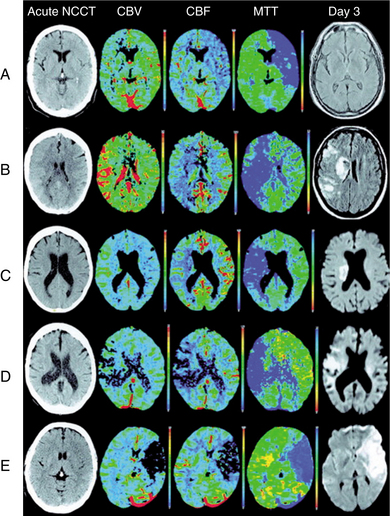

Neuroimaging of the brain has become a standard procedure in the diagnosis of stroke. Computed tomographic (CT) scan is the fastest, most convenient and widely available test to use for the diagnosis and early treatment of acute stroke. It can confirm the diagnosis and rule out other pathologies and extent of the lesion. Fig. 32-12 shows how an acute stroke looks on CT. However, CT scans may be normal in the acute stage of an embolic stroke. Bleeding into the brain tissue is seen acutely in a hemorrhagic stroke. Displacement of brain structures, such as the ventricles, by edema sometimes can be seen early in a large infarct. In ischemic stroke, CT scans reveal the area of decreased density and loss of grey/white matter differentiation resulting from edema. Cortical lesions appear wedge shaped and deeper lesions appear to be round or oval. Potential for hemorrhagic transformation of the ischemic infarct can be seen on CT.75 Lacunar infarcts are sometimes visible on CT scans as small, punched-out, hypodense areas. Images of lacunae and be seen in Fig. 32-13. Identification of the penumbra and infarct core on hyperacute noncontrast and perfusion CT may lead to potentially more aggressive treatments related to reperfusion and to arrest progression of stroke damage in the early part of the stroke.74 Fig. 32-14 demonstrates how the use of new imaging techniques may assist in this goal.

Figure 32-14 Patient A: Isolated focal swelling (IFS) on noncontrast CT (NCCT), hypoperfusion on mean transit time (MTT), and increased cerebral blood volume (CBV) on acute CT perfusion (CTP) maps, and no progression to infarction with subsequent major reperfusion. Patient B: IFS on NCCT, hypoperfusion on MTT, and increased CBV on acute CTP maps, but progression to infarction occurred without major reperfusion. Patient C: Hypoperfusion on MTT and increased CBV on acute CTP maps without any change apparent on acute NCCT. No infarction in cortical regions on follow-up with major reperfusion. Patient D: Hypoperfusion on MTT and decreased CBV on acute CTP maps without any apparent change on NCCT. Subsequent infarction present in reduced CBV regions on follow-up MRI. Patient E: Profound decrease in CBV and CBF on acute CTP maps with associated parenchymal hypoattenuation on NCCT. Extensive infarction on follow-up MRI. (Reprinted from Parsons M, Pepper EM, Bateman GA, et al: Identification of the penumbra and infarct core on hyperacute noncontrast and perfusion CT, Neurology 68(10):730-736, 2007.)